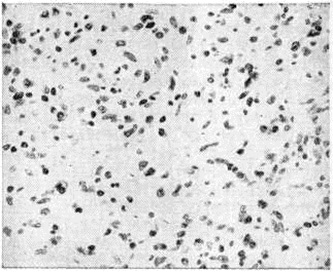

Рис. 1.

Микропрепараты лимфатического узла при лимфогранулематозе: а — клетка Березовского — Штернберга (указана стрелкой); б — клетки Ходжкина (указаны стрелками).

Микроскопическая картина Лимфогранулематоз характеризуется разрастаниями лимфоидных и плазматических клеток, гистиоцитов, фибробластов, эозинофильных и нейтрофильных лейкоцитов, пролиферацией клеток эндотелия сосудов, что в совокупности создаёт пёструю картину, напоминающую по виду строение грануляционной ткани. В ряде случаев так называемый ксантоматозного Лимфогранулематоз цитоплазма гистиоцитарных элементов содержит включения липидов. На фоне гранулематоза обнаруживаются гигантские клетки Березовского—Штернберга (рисунок 1, а), основными отличительными морфологический особенностями которых являются гигантский размер цитоплазмы и ядер, признаки деления ядра без деления цитоплазмы и крупные ядрышки, напоминающие внутриядерные включения. Ядра клеток Березовского—Штернберга крупные, диаметром 40—80 микрометров, с нежной сетью хроматина, сгущающейся к периферии, что создаёт внутри ядра центральную зону просветления. Один из вариантов клеток Березовского—Штернберга — так называемый лакунарные клетки (рисунок 3, в) с ядрами меньшей величины и обильной, очень чётко очерченной, обычно светлой, иногда оптически «пустой» цитоплазмой. Лакунарные клетки хорошо выявляются при фиксации материала в растворе формалина; использование для фиксации, например, растворов хромовых солей к такому эффекту не приводит. Клетки Березовского—Штернберга при разных морфологический типах Лимфогранулематоз встречаются в различном количестве, при этом в терминальной стадии они отличаются полиморфностью и гиперхромией ядер. Высокая специфичность для Лимфогранулематоз клеток Березовского— Штернберга послужила основанием к тому, чтобы называть их диагностическими клетками. При Лимфогранулематоз встречаются также так называемый клетки Ходжкина (рисунок 1,6) — гигантские одноядерные клетки, являющиеся, по некоторым данным, предшественниками клеток Березовского—Штернберга, но лишённые признаков деления ядра.